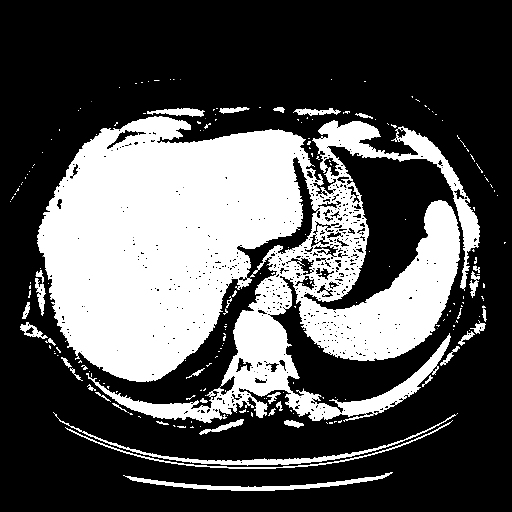

Reconstructed NATIVE CT scan (cycle consistency)

Full window (WL 1023.5, WW 4095 β†’ Low βˆ’1024, High +3071)

Actual HU range: [-1024.0, 3071.0]